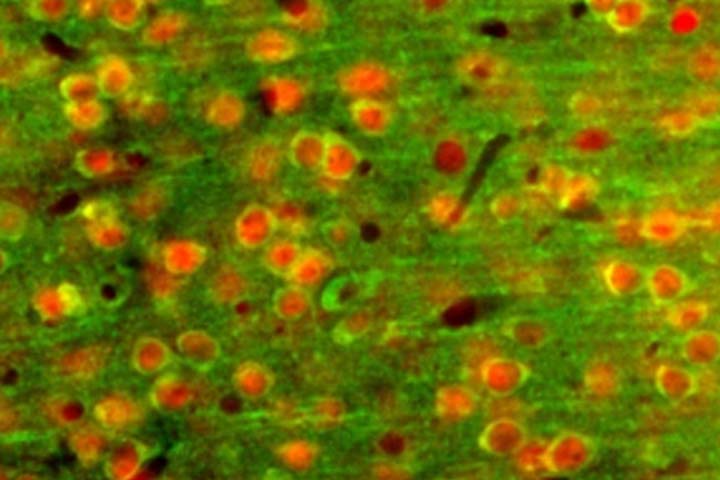

Les scientifiques sont partis d’une observation faite précédemment : les neurones du cortex somatosensoriel primaire sont actifs lorsque la peau entre en contact avec des températures froides. Ils s’attendaient donc à ce que les températures chaudes soient également codées dans cette région. Un test a ainsi été réalisé sur des souris. Pour se faire, ils ont exposé les pattes avant de ces dernières à de légers changements de température. Ils ont ensuite utilisé des techniques d’imagerie pour découvrir quelle partie du cerveau réagissait à ces changements de température. À leur grande surprise, les scientifiques ont constaté que le cortex somatosensoriel primaire ne réagissait pas à la chaleur, mais en regardant de plus près, que le cortex insulaire postérieur réagissait non seulement au froid mais aussi au chaud. L’utilisation d’un microscope à deux photons a permis d’analyser la réponse de neurones individuels dans le cortex insulaire postérieur. Les scientifiques ont ainsi découvert qu’il existe des neurones spécifiques au froid, des neurones spécifiques au chaud et des neurones qui réagissent à la fois au chaud et au froid. A noter que les neurones « chauds » et « froids » réagissent de manière très différente. En effet, les neurones « chauds » sont sensibles à la température absolue, tandis que les neurones froids sont activés suite à une variation de la température. De plus, les réponses des neurones « froids » sont plus rapides que les réponses des neurones « chaud ». Cela indique qu’il existe potentiellement des voies distinctes pour la perception du froid et du chaud.